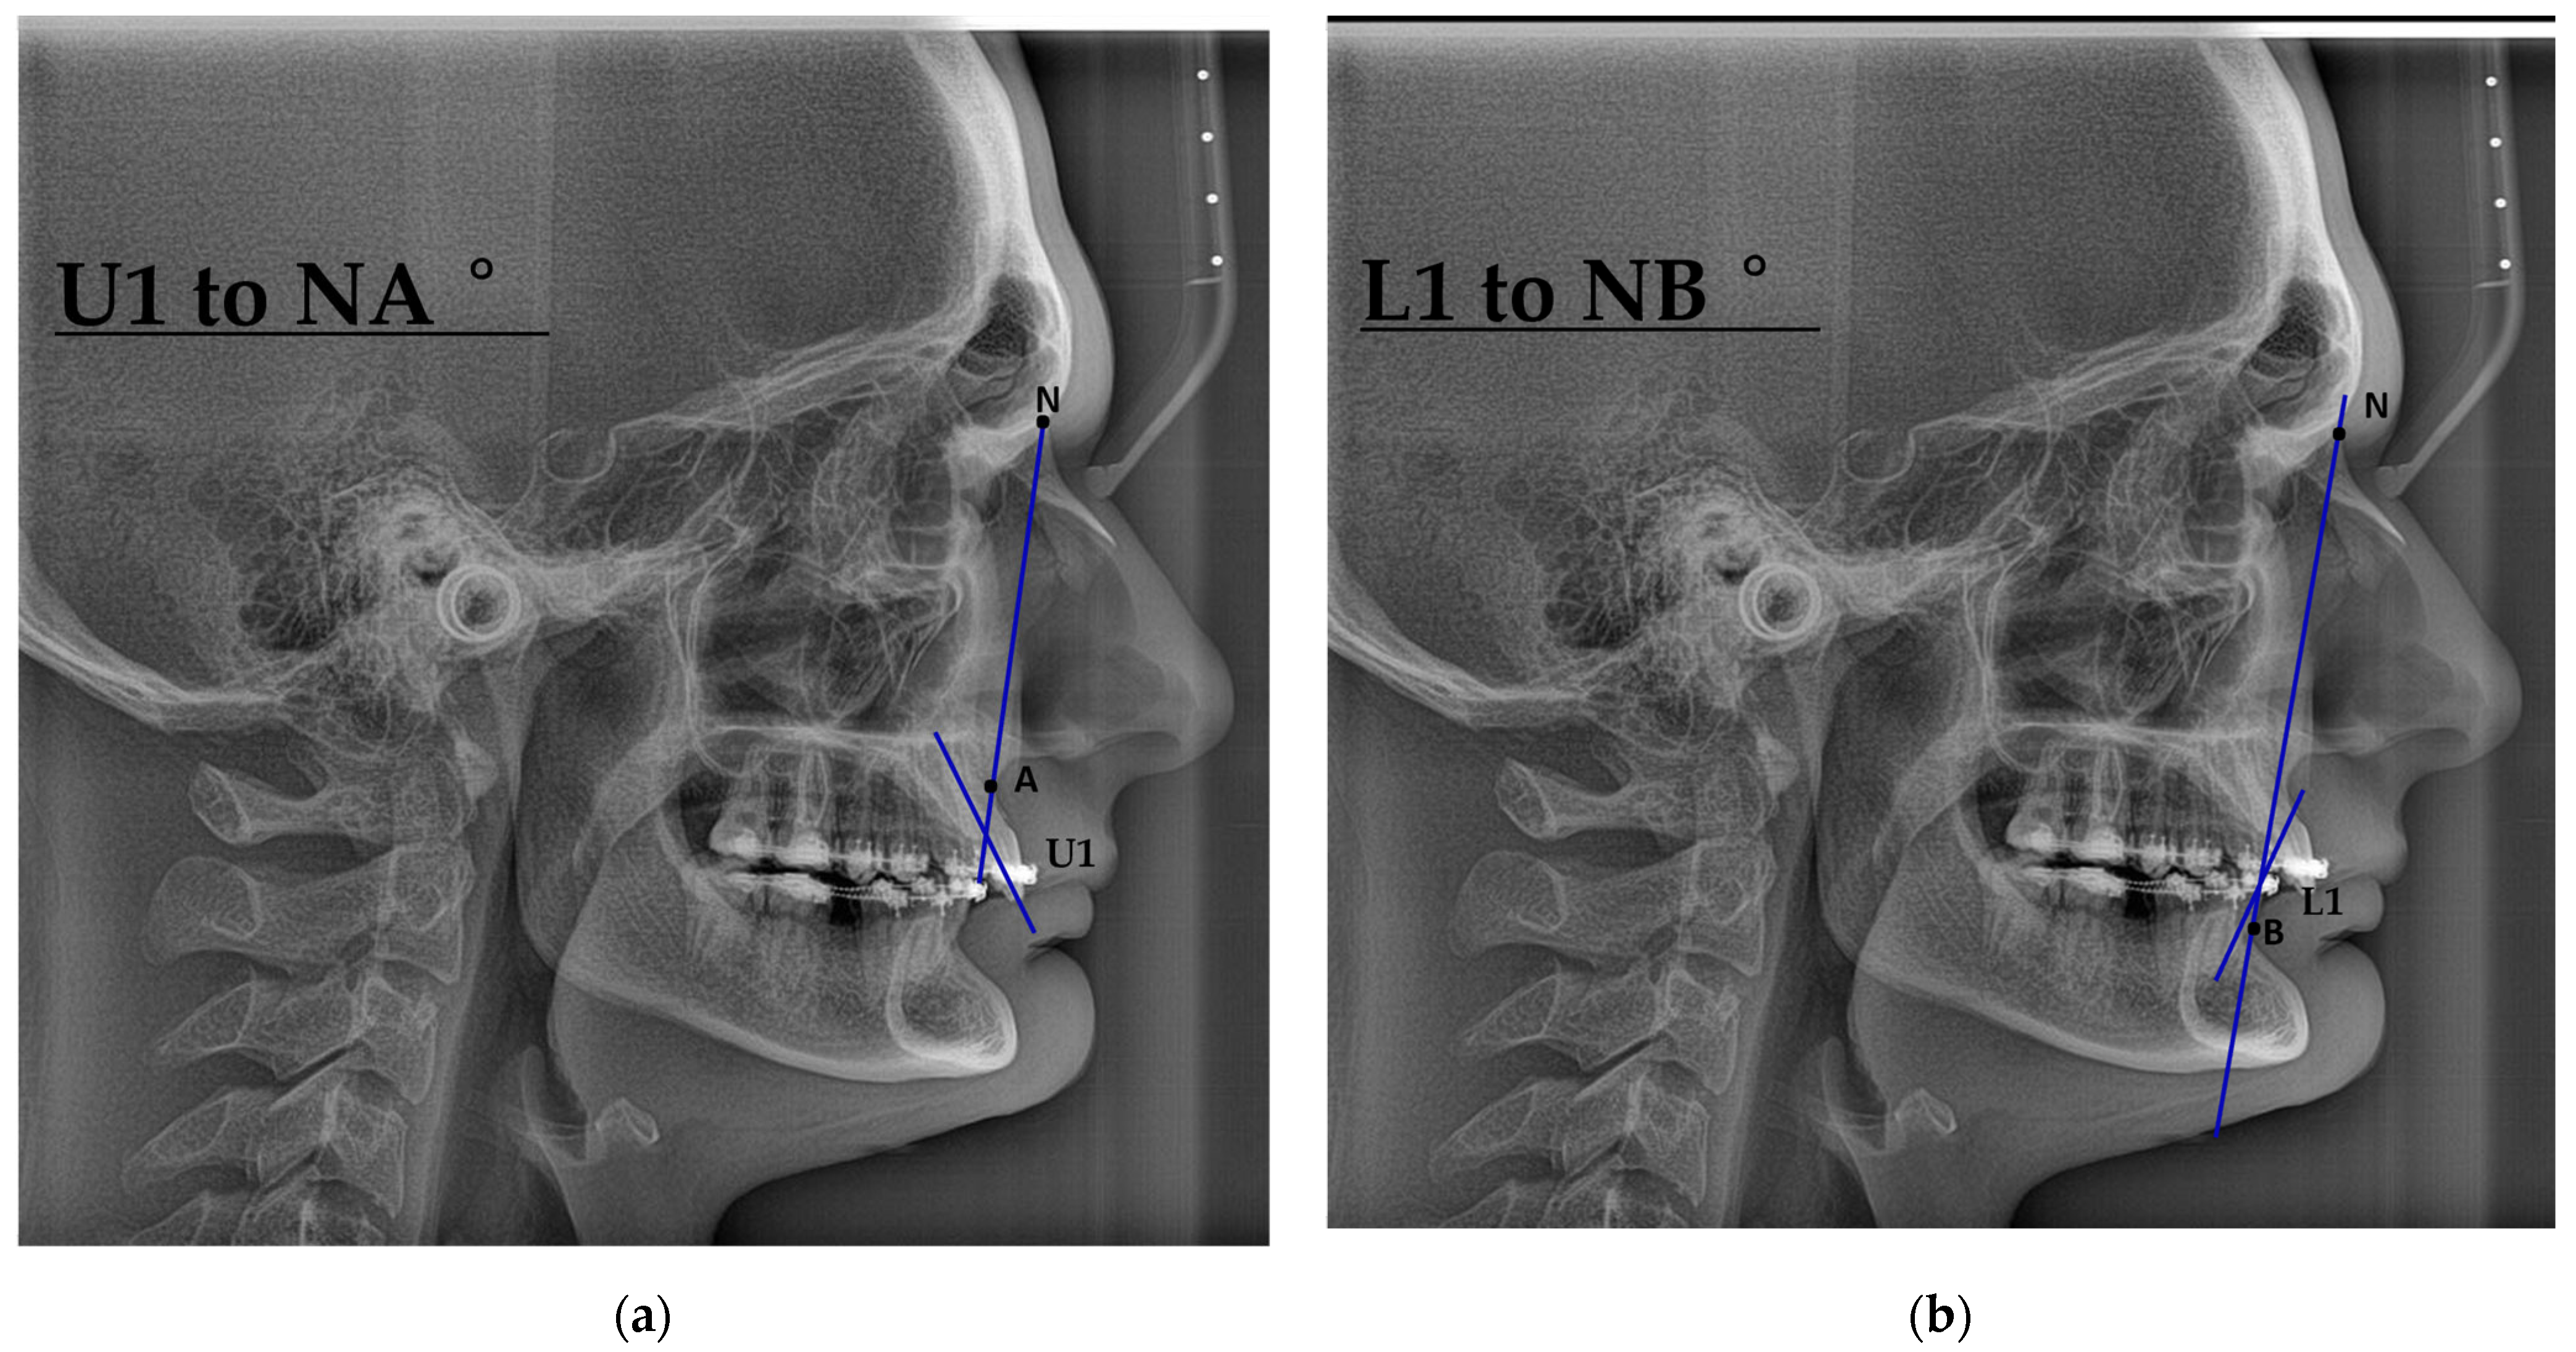

| U1–NA (°) | 26 (21, 28) | 22 (19, 29) |

| L1–NB (°) | 24 (17, 27) | 25 (19, 30) |

| U1–NA (°) | 0.465 | 1.87 | 0.249 | 24 | 0.806 |

| L1–NB (°) | −2.968 | 1.55 | −1.915 | 24 | 0.067 |